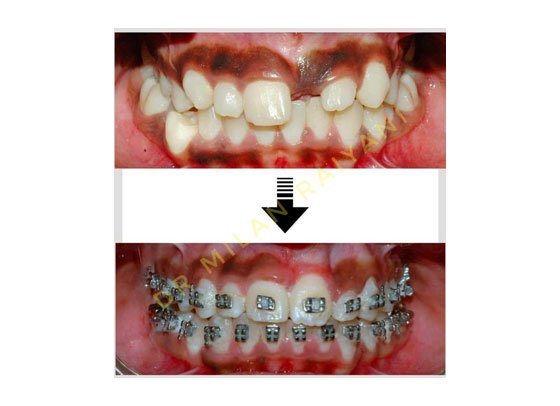

GALLERY